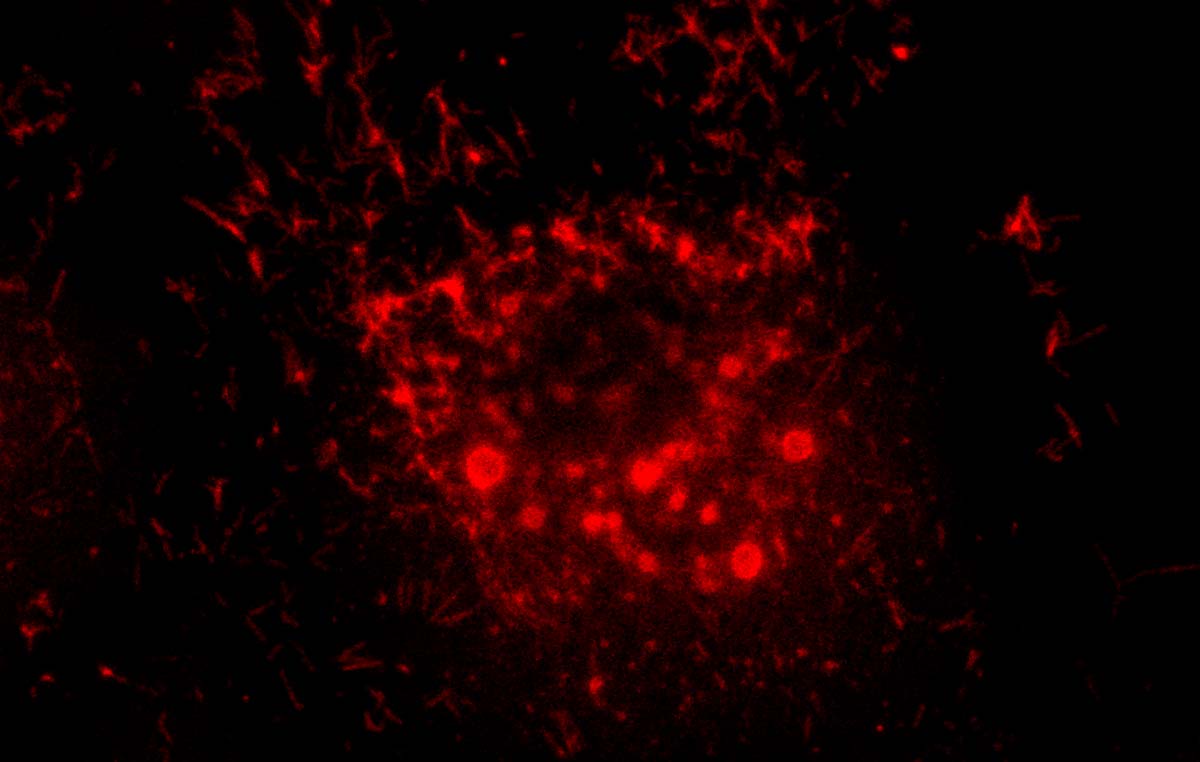

La infección de células por el VSR induce la formación de gránulos, unas estructuras que concentran todos los componentes necesarios para que el virus se multiplique.

En sus estudios, Camporeale pretende comprender el comportamiento y la distribución espaciotemporal de las proteínas que participan en la conformación de esas auténticas “fábricas virales”.

“Si bien se conocen los componentes involucrados en los gránulos que se forman después de la infección, mis investigaciones apuntan a entender de qué manera se combinan, que dominios participan y como se forman en la escala de tiempo”, explica la bioquímica graduada en la UBA y doctorada en la Universidad de Nebraska-Lincoln, en Estados Unidos.

La posibilidad de caracterizar las proteínas que conforman las fábricas virales podrá contribuir a establecer métodos de screening (tamizaje) para compuestos con actividad antiviral, así como podrá ayudar en la búsqueda de blancos terapéuticos para el desarrollo de antivirales y en la producción de herramientas diagnósticas, señaló Camporeale.